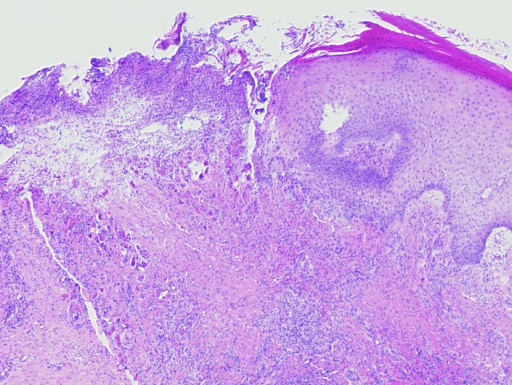

Da die beteiligten Granulozyten beim Durchwandern der Gefäßwände selbst zugrunde gehen, bezeichnet man diese Erkrankung auch als leukozytoklastische Vaskulitis (Abb. 3).

Abb. 3: Histologischer Befund einer leukozytoklastischen Vaskulitis in der Übersicht, die Epidermis ist partiell zerstört und abgehoben, es besteht ein massives zelluläres Infiltrat der Dermis (a). In den Gefäßen und den Gefäßwänden finden sich segmentkernige Granulozyten. Fibrinoide Nekrose der Gefäßwände und zerfallende Granulozyten, die auch perivaskulär abgelagert sind (b,c). Residuale Obstruktion und Infarzierung kleiner kutaner Blutgefäße (d,e).